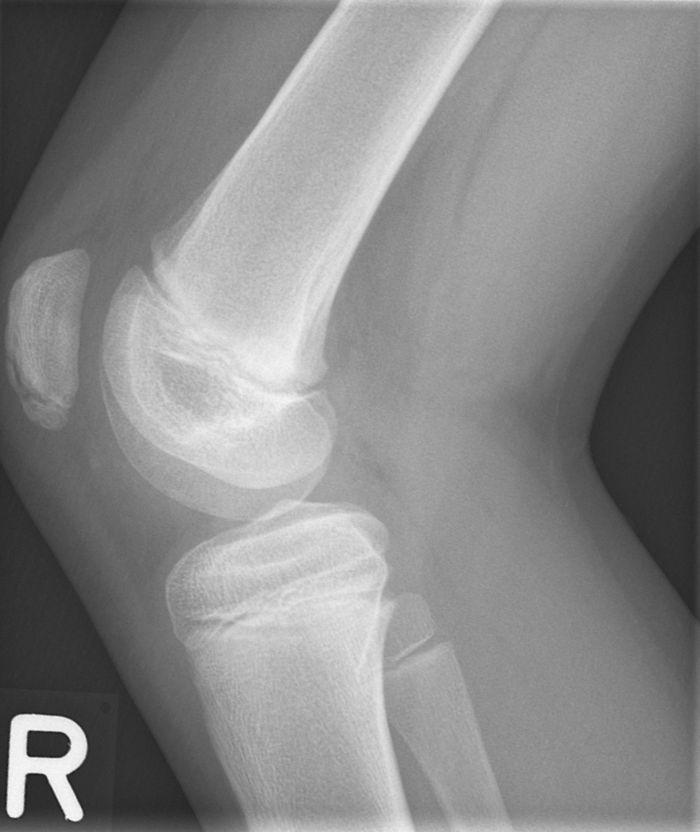

Een 12-jarige jongen presenteerde zich met pijnklachten van de rechter patella na elke voetbalwedstrijd. Anamnestisch was er geen evident trauma. Bij lichamelijk onderzoek was er sprake van een neutrale beenas, symmetrische kniecontouren, geen hydrops, een maximale kniefunctie met niet-afwijkende stabiliteit. Alleen rechts was er lokale drukpijn van de patella-onderpool.

Wat is uw diagnose?